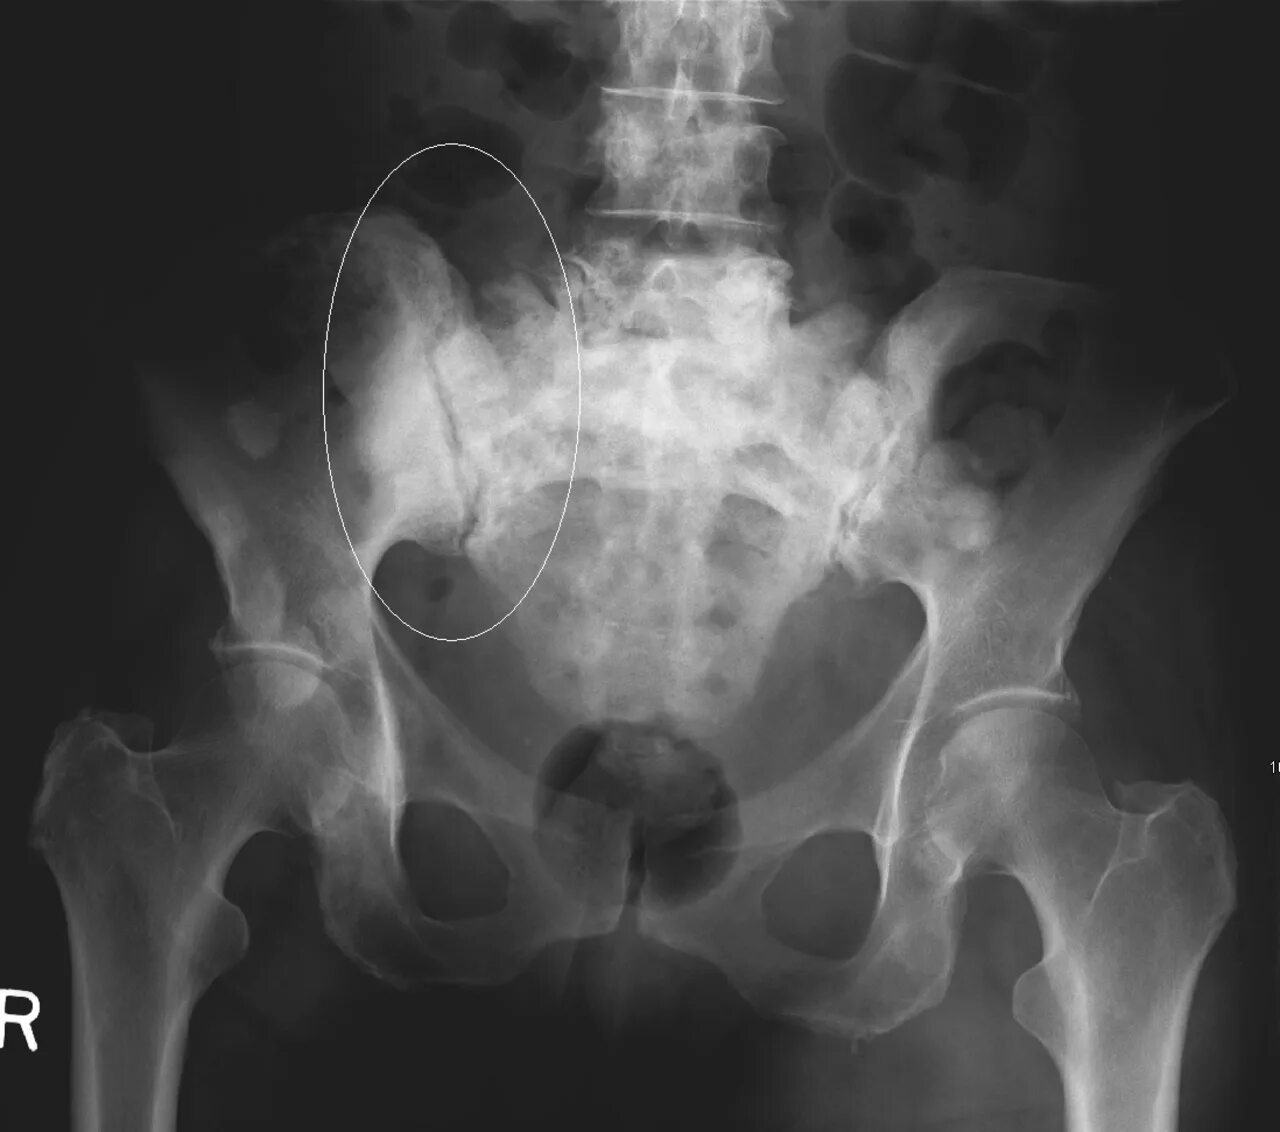

Метастазы в костях какая стадия